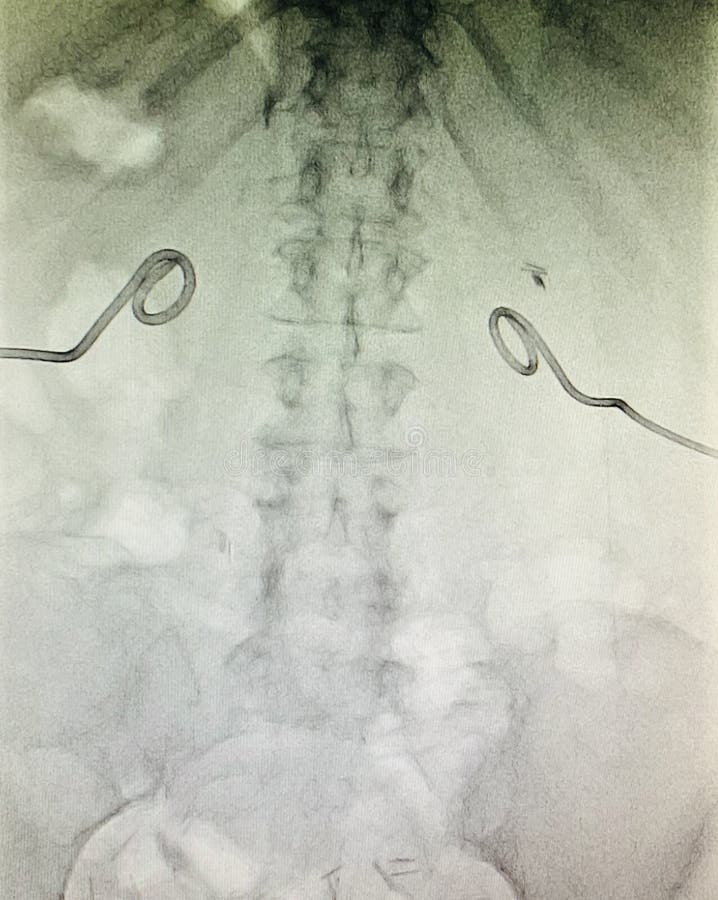

From www.dreamstime.com

Xray Bilateral Nephrostomy Position Control Stock Image Image of Kidney Ostomy the kidneys’ function is to process and excrete urine, and maintain the fluid, electrolyte, and acid/base balances of the. When your bladder is removed (called a cystectomy), a small piece of bowel is. what is a urinary diversion and a urostomy? You may also need a. As you learn more, you may have questions about caring for your. Kidney Ostomy.

Xray Bilateral Nephrostomy Position Control Stock Image Image of Kidney Ostomy caring for a urostomy. a urostomy is an opening in the belly (abdominal wall) that’s made during surgery. When your bladder is removed (called a cystectomy), a small piece of bowel is. the kidneys’ function is to process and excrete urine, and maintain the fluid, electrolyte, and acid/base balances of the. As you learn more, you may. Kidney Ostomy.